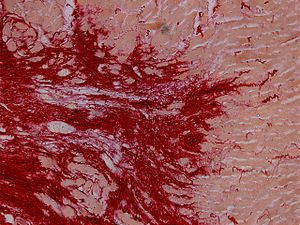

Histopathology

Histopathological examination of the heart may reveal infarction at autopsy. Under the microscope, myocardial infarction presents as a circumscribed area of ischemic, coagulative necrosis (cell death). On gross examination, the infarct is not identifiable within the first 12 hours.

Although earlier changes can be discerned using electron microscopy, one of the earliest changes under a normal microscope are so-called wavy fibers. Subsequently, the myocyte cytoplasm becomes more eosinophilic (pink) and the cells lose their transversal striations, with typical changes and eventually loss of the cell nucleus. The interstitium at the margin of the infarcted area is initially infiltrated with neutrophils, then with lymphocytes and macrophages, who phagocytose ("eat") the myocyte debris. The necrotic area is surrounded and progressively invaded by granulation tissue, which will replace the infarct with a fibrous ( collagenous) scar (which are typical steps in wound healing). The interstitial space (the space between cells outside of blood vessels) may be infiltrated with red blood cells.

These features can be recognized in cases where the perfusion was not restored; reperfused infarcts can have other hallmarks, such as contraction band necrosis.